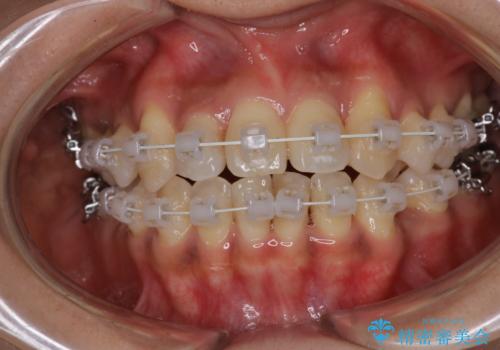

【審美装置】抜歯の本数最小限で行った矯正治療

- 治療計画

- 全体のがたつきを主訴に来院されました。4番目の歯を4本抜歯も検討しましたが、口元が下がりすぎてしまうリスクと2番目の転位うが著しく並べるのにかかる期間を考慮し、変則的な抜歯をし、並べる計画を立てました。

抜歯矯正のため2年はかかってしまいましたが、きれいに並び患者様にも満足頂きました。